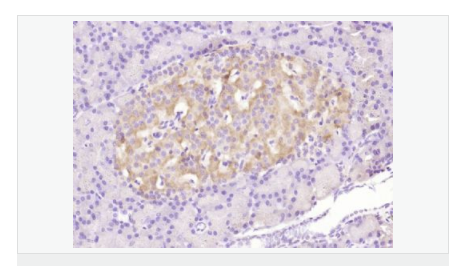

交叉反應(yīng):Human,Mouse,Rat(predicted:Dog,Pig,Cow,Sheep) 推薦應(yīng)用:WB,IHC-P,Flow-Cyt,ELISA

產(chǎn)品應(yīng)用WB=1:500-2000 ELISA=1:5000-10000 IHC-P=1:100-500 Flow-Cyt=3μg /test (石蠟切片需做抗原修復(fù))

免 疫 原KLH conjugated Synthesised phosphopeptide derived from human Bax around the phosphorylation site of Ser184:TA(p-S)LT

產(chǎn)品介紹The protein encoded by this gene belongs to the BCL2 protein family. BCL2 family members form hetero- or homodimers and act as anti- or pro-apoptotic regulators that are involved in a wide variety of cellular activities. This protein forms a heterodimer with BCL2, and functions as an apoptotic activator. This protein is reported to interact with, and increase the opening of, the mitochondrial voltage-dependent anion channel (VDAC), which leads to the loss in membrane potential and the release of cytochrome c. The expression of this gene is regulated by the tumor suppressor P53 and has been shown to be involved in P53-mediated apoptosis. Multiple alternatively spliced transcript variants, which encode different isoforms, have been reported for this gene. [provided by RefSeq, Jul 2008].

Accelerates programmed cell death by binding to, and antagonizing the apoptosis repressor BCL2 or its adenovirus homolog E1B 19k protein. Under stress conditions, undergoes a conformation change that causes translocation to the mitochondrion membrane, leading to the release of cytochrome c that then triggers apoptosis. Promotes activation of CASP3, and thereby apoptosis.

Subcellular Location:

Tissue Specificity: